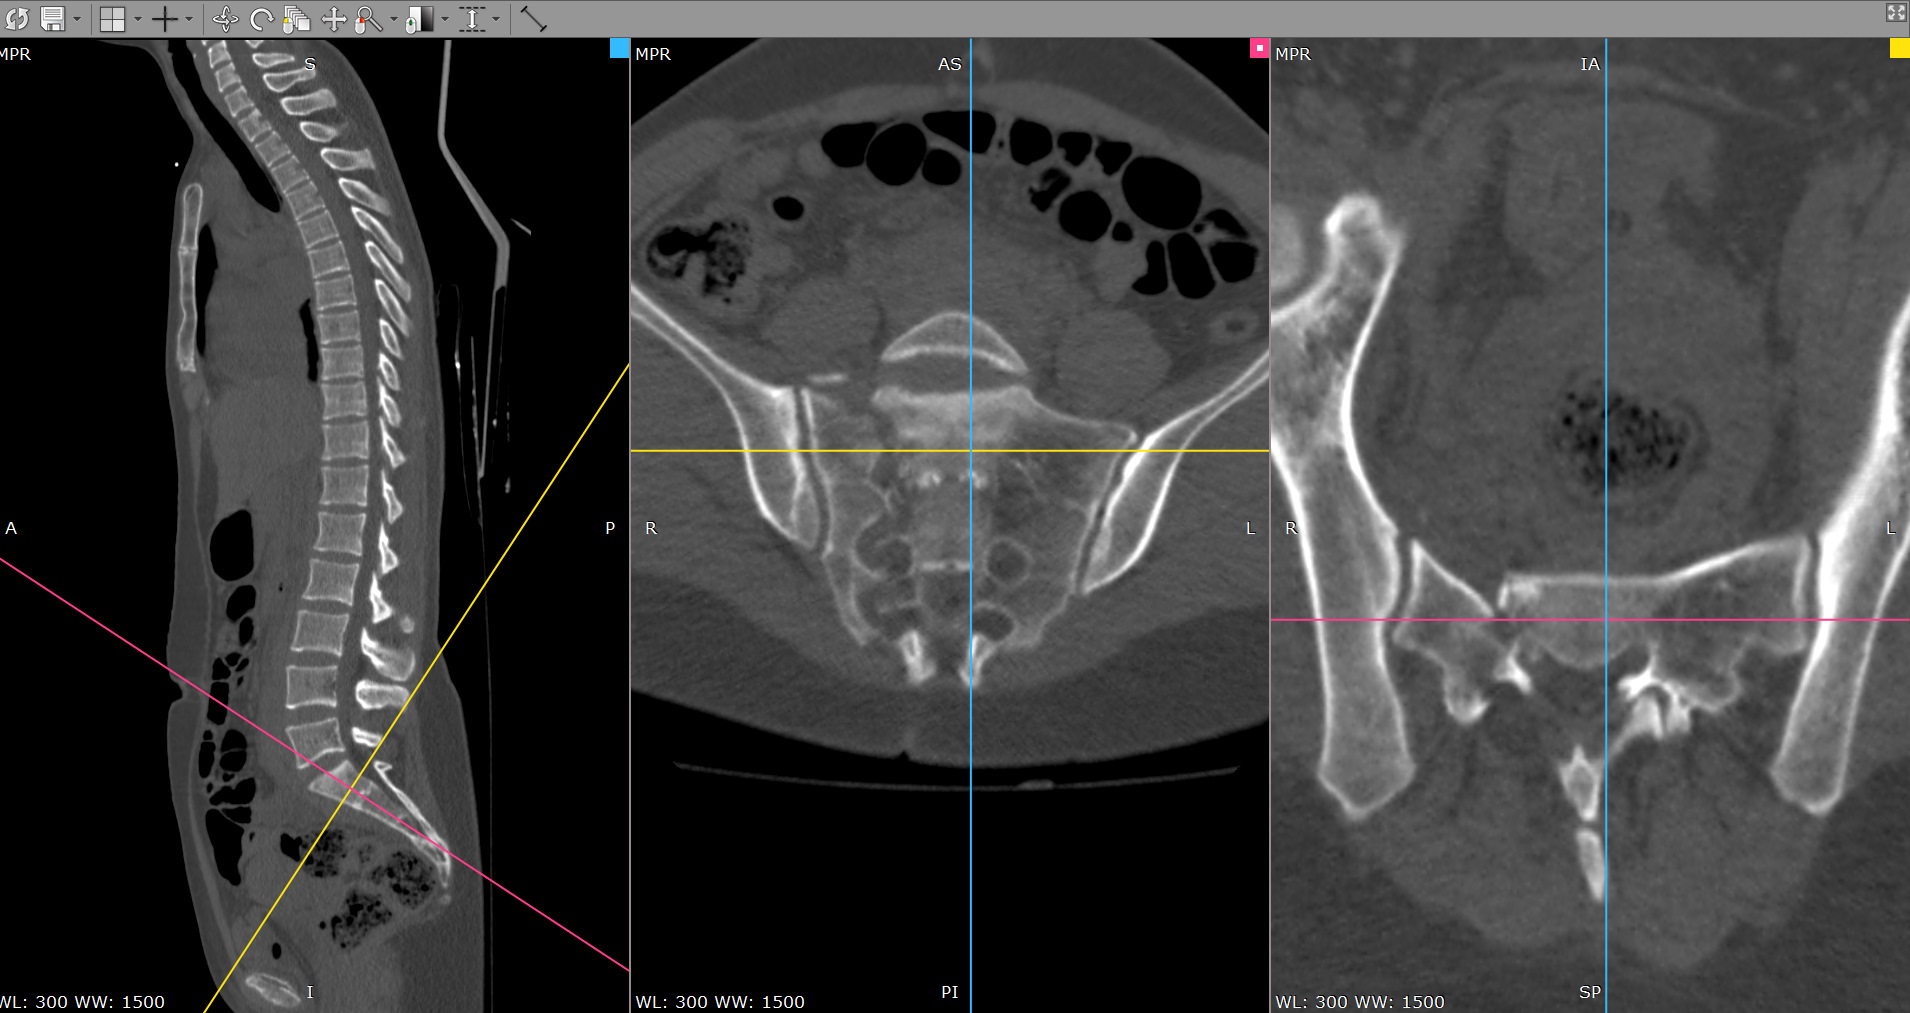

Боковая масса крестца что это 56 фото